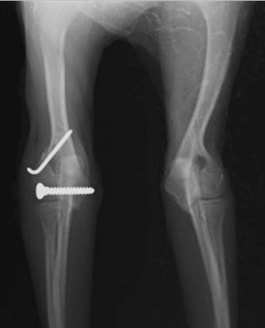

他院にて左大腿骨遠位の成長板骨折(salter-harrisⅠ型)が認められており、治療相談を目的として来院。当院にて、キルシュナーワイヤーを用いたピンニングにより骨折部位の整復を行いました。術後の経過は良好で、現在も経過観察中です。

術後レントゲン

Arthrex社のターゲティングデバイスを用いてピンニングの位置を調整することで、確実な固定を行っています。当院ではこの手術器具以外にも、人の手術にも使用される様々な器具を導入し、手術精度を高め、また医療メーカーと新しい器具の開発、試作にも取り組んでおります。